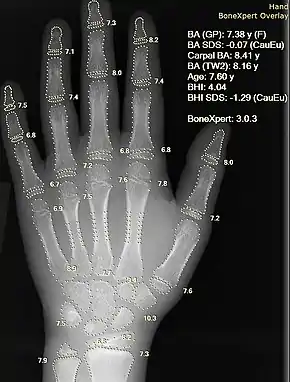

Image and sound processing

Information can take the form of images, sound, video or other multimedia. Bits of information can be streamed via signals. Its processing is the central notion of informatics, the European view on computing, which studies information processing algorithms independently of the type of information carrier – whether it is electrical, mechanical or biological. This field plays important role in information theory, telecommunications, information engineering and has applications in medical image computing and speech synthesis, among others. What is the lower bound on the complexity of fast Fourier transform algorithms? is one of unsolved problems in theoretical computer science.

| FFT algorithms | Image processing | Speech recognition | Data compression | Medical image computing | Speech synthesis |